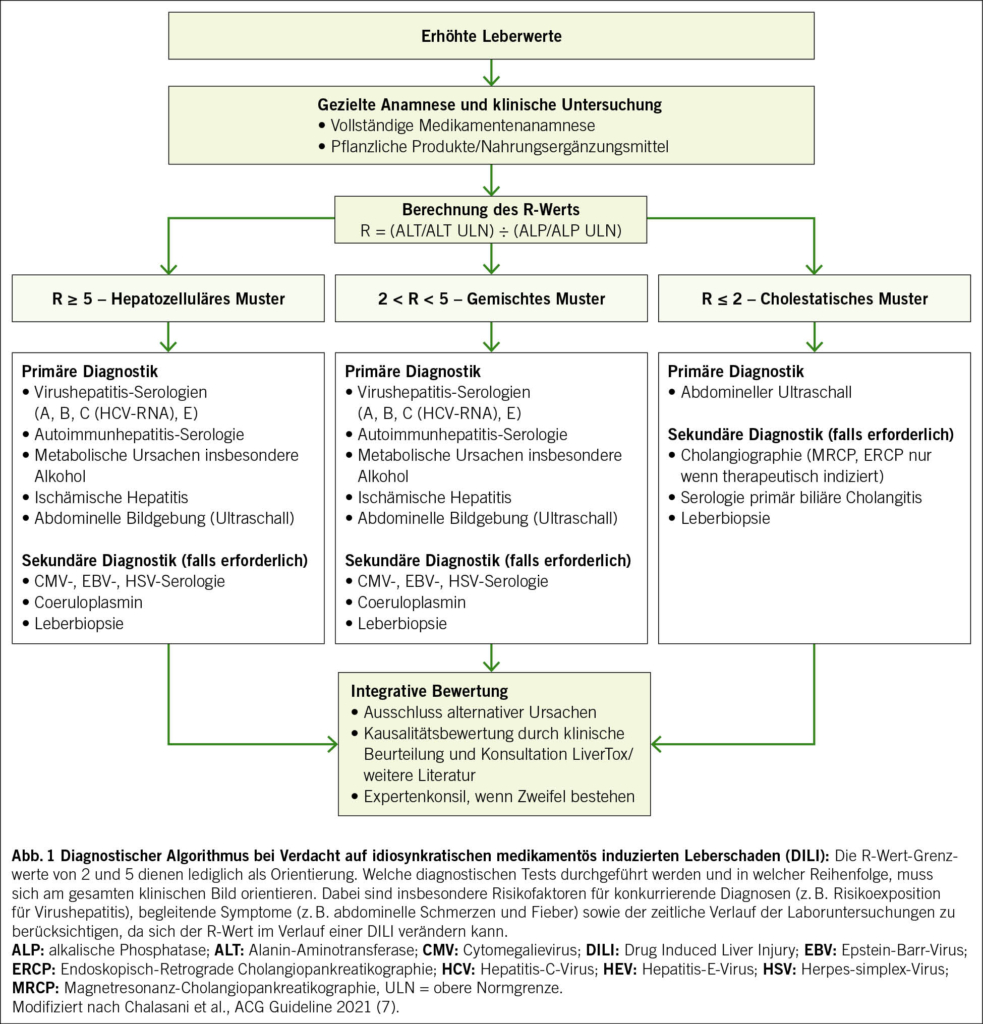

Schädigungsmuster und klinische Bedeutung des R-Werts

Zur weiteren Einordnung hat sich die Bestimmung des R-Werts etabliert, berechnet aus dem Verhältnis ALT/ULN zu ALP/ULN. Er erlaubt die Einteilung in hepatozelluläre (R ≥ 5), cholestatische (R ≤ 2) und gemischte Schädigungsmuster (R 2–5). Diese Klassifikation besitzt diagnostische und prognostische Relevanz. Hepatozelluläre Muster sind häufiger mit schweren Verläufen assoziiert, insbesondere bei zusätzlichem Ikterus. Cholestatische Verläufe präsentieren sich typischerweise mit Pruritus und zeigen meist einen protrahierten, insgesamt jedoch günstigeren Verlauf. Gemischte Muster vereinen Merkmale beider Entitäten. Entsprechend sollten Differenzialdiagnosen gezielt priorisiert werden, etwa virale Hepatitiden oder ischämische Leberschäden bei hepatozellulärem Muster und biliäre Obstruktionen bei cholestatischem Verlauf (7, 8). Zu beachten ist, dass einzelne Medikamente unterschiedliche Muster verursachen können. Ein strukturiertes diagnostisches Vorgehen ist in Abb. 1 dargestellt.